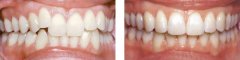

孩子前牙拥挤有危害吗?

前牙拥挤在牙颌畸形中是较为常见的。前牙拥挤的原因主要是颌骨前部发育不足...【详细】

牙齿拥挤要怎么修复?

牙齿拥挤是常见的错合畸形,表现为牙齿拥挤错位排列不齐;而拥挤牙齿的龋及...【详细】